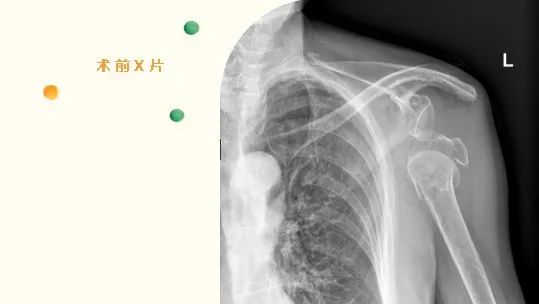

2022年6月,82岁的刁奶奶,因“摔伤致左肩部疼痛伴活动受限2+小时”入住我院骨伤科。入院后,骨伤科许锦涛主治医师通过详细的查体及相关辅助检查,诊断刁奶奶为“1.骨质疏松伴左肱骨近端粉碎性骨折2.左肩关节脱位”。

骨伤科张成勇主任召集全科室对患者进行讨论研究,经讨论,一致考虑患者年龄较大,基础疾病较多,尤其是有糖耐量受损及严重骨质疏松,骨折粉碎程度高且合并巨大肩袖撕裂,传统骨折切开复位钢板内固定术难以有效固定骨折断端,人工肱骨头置换术术后难以改善肩关节功能,容易出现内固定松动失效、骨折不愈合等问题,经过和患者、家属充分沟通,决定采取“人工反式肩关节置换术”。

经过周密的术前准备,张成勇主任团队邀请四川省人民医院卢冰主任现场指导,顺利完成了手术,术中成功置入左侧反置式人工全肩关节假体,术后复查左肩DR,见假体位置良好,并在术后对病人进行康复训练。术后刁奶奶感疼痛明显减轻,正逐步康复锻炼,肩关节功能持续好转。